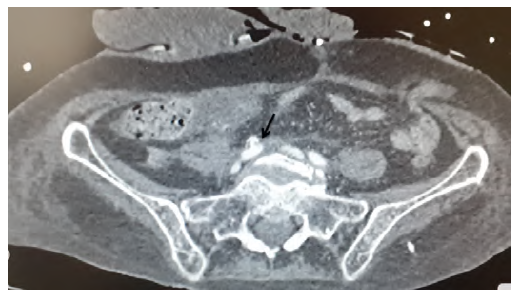

A 84-year-old female, with history of lupus, underwent pelvic exenteration, lymphadenectomy and cutaneous ureteroileostomy for high-grade urothelial carcinoma. In the postoperative period, an ileostomy with reconstruction of ureteroileal anastomoses and bilateral nephrostomies was required due to intestinal dehiscence with an abscess. She completed broad-spectrum antibiotics and antifungal therapy and was discharged with catheterized ureters. About 4 months later, the patient presented to the emergency department (ED) with gross hematuria. The blood work revealed 11g/dl of haemoglobin. Having been discharged, she returned to the ED the next day, hypotensive (94/61mmHg) with significant hematuria from ureteroileostomy, while haemoglobin had dropped to 8 g/dl, requiring aminergic support and the transfusion of two units of blood. Computed tomography (CT) angiography did not identify active bleeding and suggested integrity of the excretory system. She remained hospitalized under surveillance until she had another episode of hemorrhagic shock (blood pressure 49/23mmHg) with profuse bleeding through the ureteroileostomy, with a drop of hemoglobin to 5.5 g/dl. A new CT angiography was performed identified a fistula between the right common iliac artery and the ureteroileostomy (Figures 1 and 2). She underwent emergency angiography and fistula exclusion with a covered stent with intentional hypogastric coverage (the contralateral hypogastric was patent) given the short sealing length and the imminent risk of death (Figure 3). During the remaining hospital stay, there were no bleeding recurrences, and the patient was discharged on the 21st postoperative day after completing antibiotic therapy (meropenem and linezolid) and antifungal medication (micafungin) directed to urine cultures (isolated: multidrug resistant Staphylococcus aureus, Enterococcus faecium, Candida albicans). About one month later she was hospitalized again for acute kidney injury with ionic changes and complicated urinary tract infection, ending up dying from this complication.

Figure 1 Preoperative computed tomography angiography (cross sectional). Right common iliac artery-ureter fistula on cross sectional computed tomography angiography (black arrow)